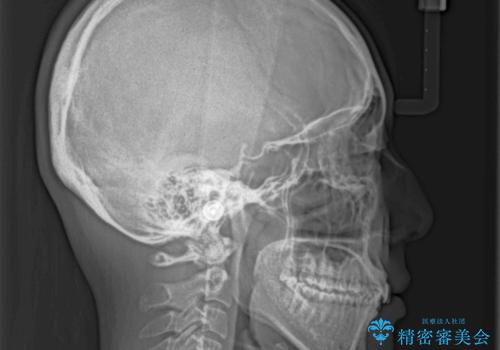

- 深い咬み合わせ(ディープバイト)と前歯のデコボコを気にして来院された患者様です。

インビザラインによる上下歯列の側方拡大と後方移動、IPR(歯と歯の間を削る)にるスペースの獲得により、デコボコとディープバイトを改善することとしました。

後方移動に際し、下顎の親知らずは2本とも抜歯することとしました。